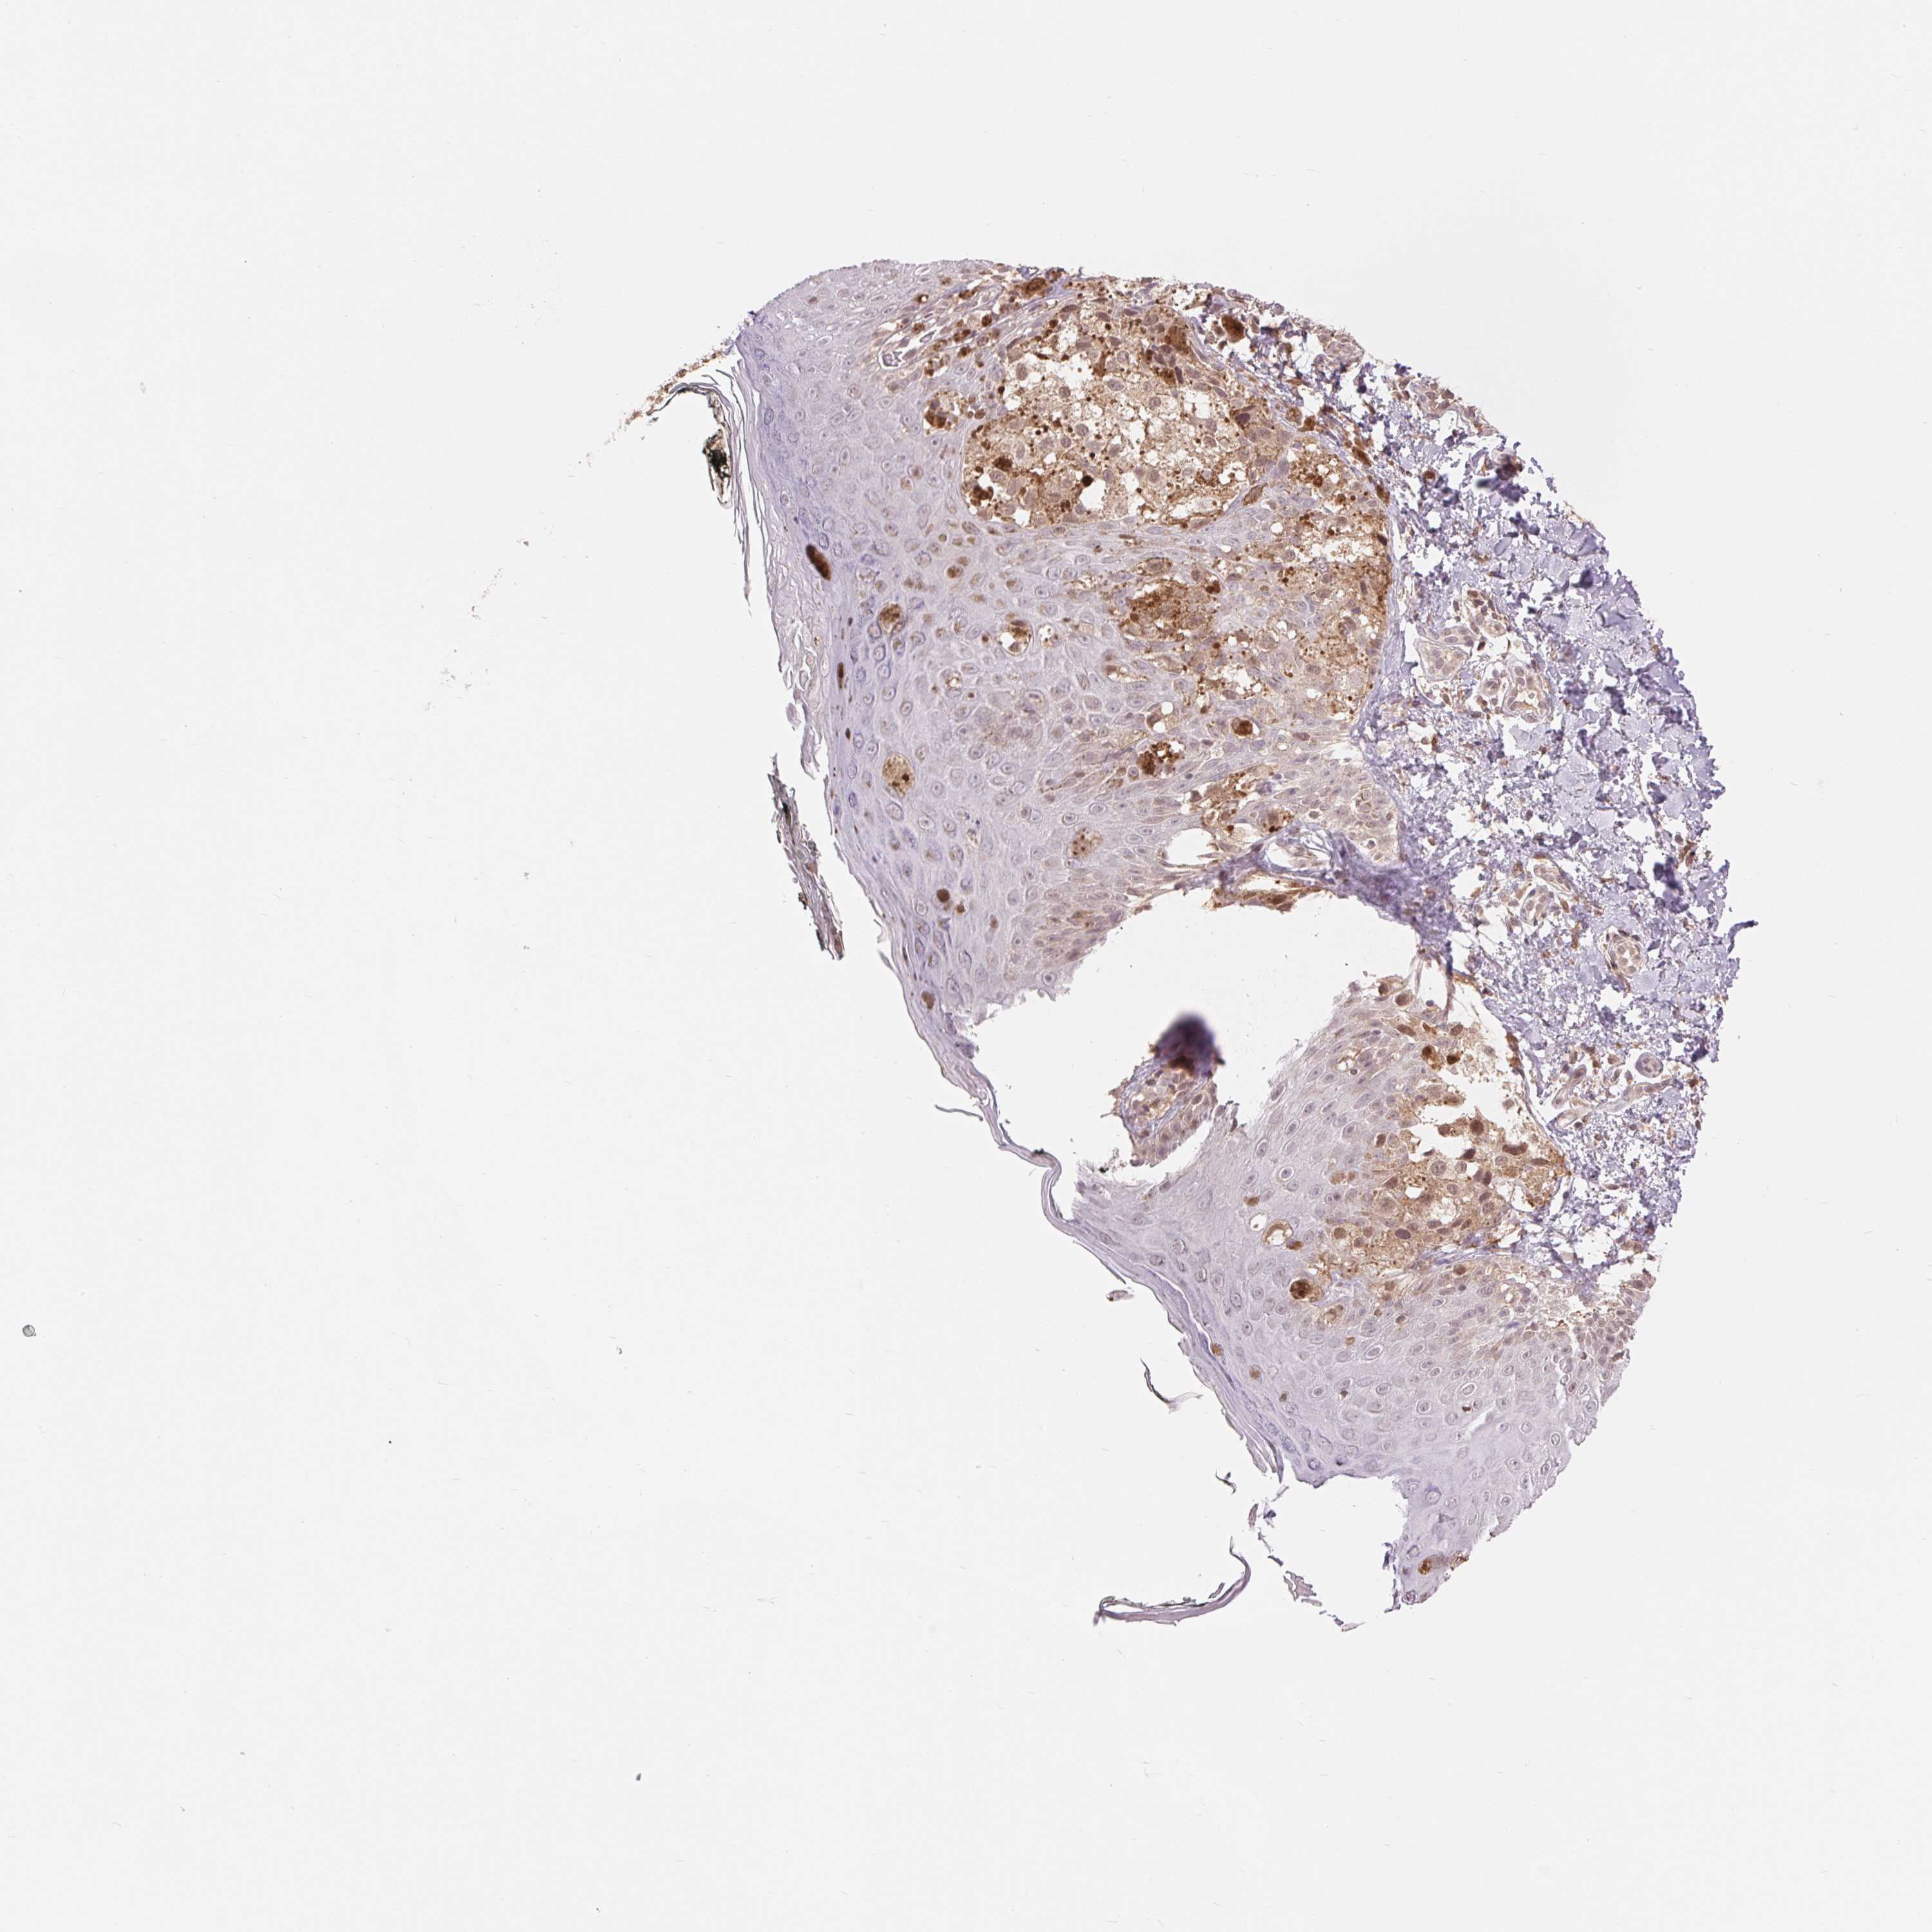

MELANOMA - Protein expressioni

A mouse-over function shows sample information and annotation data. Click on an image to view it in a full screen mode. Samples can be filtered based on level of antibody staining by selecting one or several of the following categories: high, medium, low and not detected. The assay and annotation is described here.

Note that samples used for immunohistochemistry by the Human Protein Atlas do not correspond to samples in the TCGA dataset.

Antibody stainingi

Antibody staining in the annotated cell types in the current human tissue is reported as not detected, low, medium, or high, based on conventional immunohistochemistry profiling in selected tissues. This score is based on the combination of the staining intensity and fraction of stained cells.

Each image is clickable and will lead to virtual microscopy that enables deeper exploration of all samples and also displays staining intensity scores, fraction scores and subcellular localization as well as patient and tissue information for each sample.

Antibody HPA058166

Staining

High

Medium

Low

Not detected

Intensity

Strong

Moderate

Weak

Negative

Quantity

>75%

75%-25%

<25%

None

Location

Nuclear

Cytoplasmic/membranous

Cytoplasmic/membranous,nuclear

Malignant melanoma, NOS

Malignant melanoma, Metastatic site